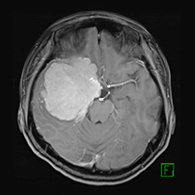

症例2) 31歳女性、頭蓋底部巨大髄膜腫、外科手術+放射線治療

<画像所見>

腫瘍はほとんど消失している。術後患者様は右眼瞼下垂、複視(動眼神経麻痺)生じたが、自宅退院された。